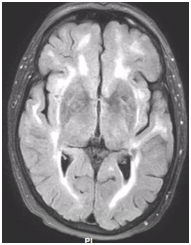

During follow-up in stroke clinic, her imaging was reviewed. MR imaging demonstrated large confluent areas of hyperintense T2 and FLAIR signal abnormality throughout the periventricular and deep white matter with extension into the subcortical white matter (Figure 1) (Figure 2). T1w images demonstrated low signal, corresponding to the T2/FLAIR abnormality on T2w images. This white matter abnormality is known as leukoaraiosis. The hyperintense T2/FLAIR signal abnormality also involved the anterior temporal lobes (Figure 3) (Figure 4) and external capsules (Figure 5) (Figure 6). This feature on MRI is uncharacteristic of other white matter diseases, notably the sporadic subcortical atherosclerotic encephalopathy. In our patient, the corpus callosum was spared. The lacunar infarcts were small vessel infarcts, typically seen in the deep white matter, basal ganglia, thalami, and the pons. On diffusion images, there was a small area of diffusion restriction in the left corona radiata that was consistent with an acute infarct (Figure 7) (Figure 8). Subsequently, there was an area of encephalomalacia on follow-up MRI at the location of the previous acute infarct. This abnormality correlated with the right-sided weakness seen prior to the index patient’s admission.

Figure 2 FLAIR axial image at a higher level demonstrates more conspicuous hyperintense white matter signal abnormality.